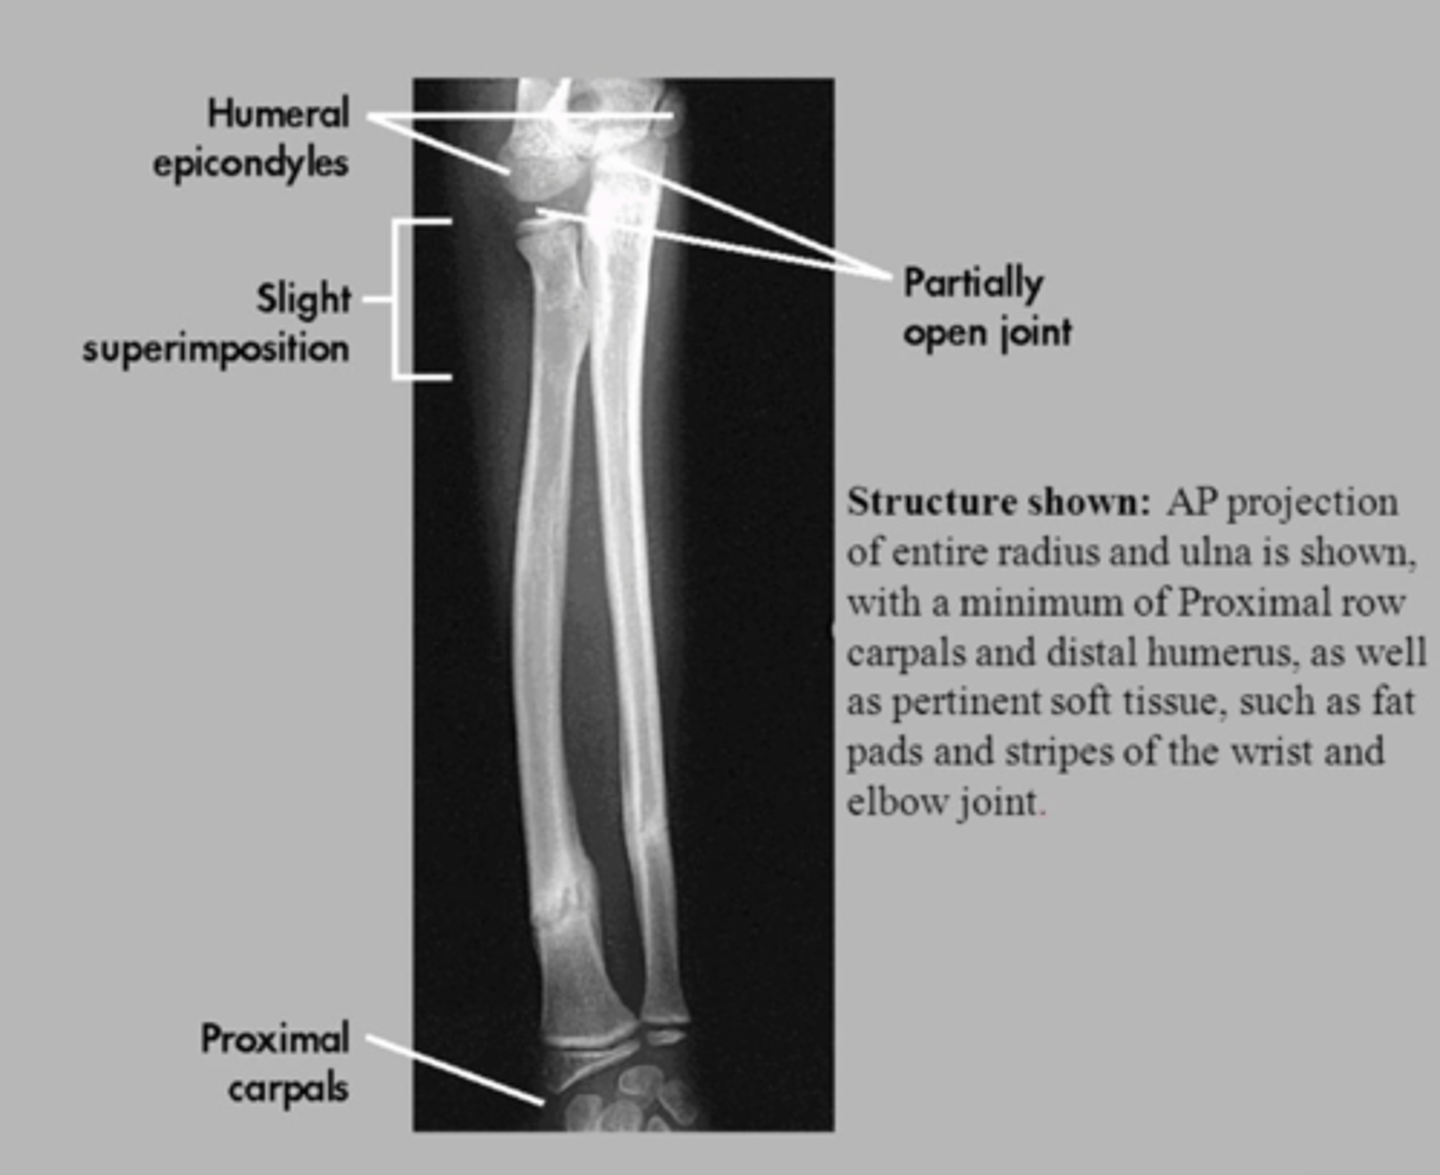

What radiographic projections are used for studying the forearm?

The forearm is studied using AP (anteroposterior) and lateral projections.

Describe the shape and curvature of the radius.

The body of the radius is prismoid in form, narrower above than below, and slightly curved, being convex lateralward.

How does the radius appear in lateral vs AP projections?

lateral projection: relatively straight

AP projection: presents discrete external convexity

Describe the ulna's morphology in lateral vs AP projections.

lateral projection: curved morphology

AP projection: relatively straight.

Compare the proximal and distal regions of the radius and ulna in terms of size.

The head of the radius is relatively small compared to its distal epiphysis, while the ulna's proximal region is larger than its distal region.